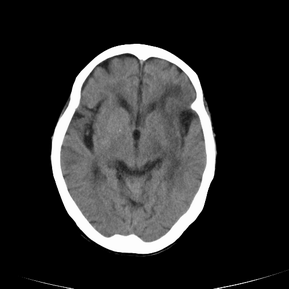

以下是引用jsgdoctor在2008-7-16 23:11:00的发言:[br]左侧大脑中动脉供血区脑梗塞